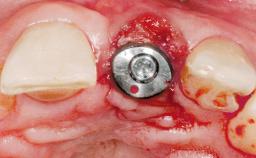

A 30-year-old female patient had lost tooth 21 and was referred to our clinic for consultation and treatment. Due to advanced apical infection, tooth 21 had been extracted two months earlier at another clinic and an acrylic-resin tooth had been bonded to the adjacent teeth. The patient desired implant treatment to avoid any damage to the adjacent natural teeth. While the patient had no history of any systemic disorder, she was a heavy smoker and exhibited medium to advanced periodontitis in the entire jaw. After the initial treatment to achieve a pocket probing depth of less than 4 mm and no bleeding on probing, a decrease in the height of the papillae mesial and distal to the extraction site and overall gingival recession were observed.

| Type of Implants | One-Piece|Reduced-Diameter |

| Bone Augmentation | Horizontal|Staged |

| Augmentation Materials | Autogenous chips|Membrane |

| Soft Tissue Grafting | Simultaneous |